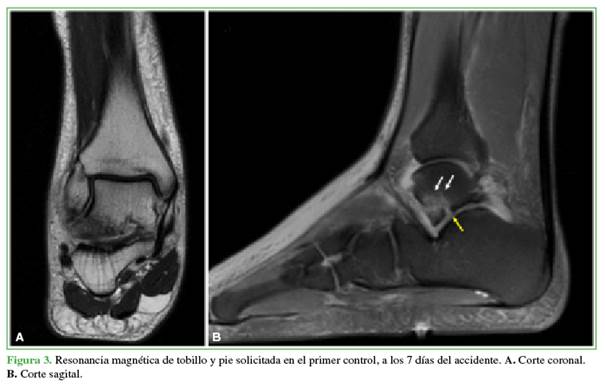

Había sufrido un trauma de tobillo derecho por una caída en una motocicleta de enduro 20 días antes. Fue evaluado en un Servicio de Urgencia el día del accidente donde le tomaron radiografías (Figura 2). Sin un diagnóstico de certeza se le indicó inmovilización con bota walker y restricción de la carga de peso. Fue examinado nuevamente a los siete días del trauma, se le solicitó una resonancia magnética de tobillo y pie (Figura 3) y se le indicó fisioterapia y descarga progresiva del peso. El dolor aumentó progresivamente, y el edema y la impotencia funcional persistían, por lo que decidió buscar una segunda opinión.

En la resonancia magnética de tobillo y pie, se detectan focos de edema óseo postraumático en el sector plantar del cuello y el cuerpo astragalino (Figura 3B, flechas blancas) y una fractura articular oblicua con edema óseo perifracturario sobre el proceso lateral del astrágalo, que compromete la articulación subastragalina posterolateral sin desplazamiento significativo de fragmentos (Figura 3B, flecha amarilla).